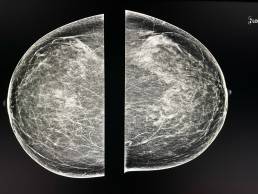

63-year-old woman, screening mammogram.

MammoScreen® points to a cluster of fine pleomorphic microcalcifications, located deep retroareolar in the left breast. MammoScreen score™ 9: highest suspicion.

This cluster did not exist on the previous mammogram.

Marcrobiopsy finds intraductal carcinoma lesions.